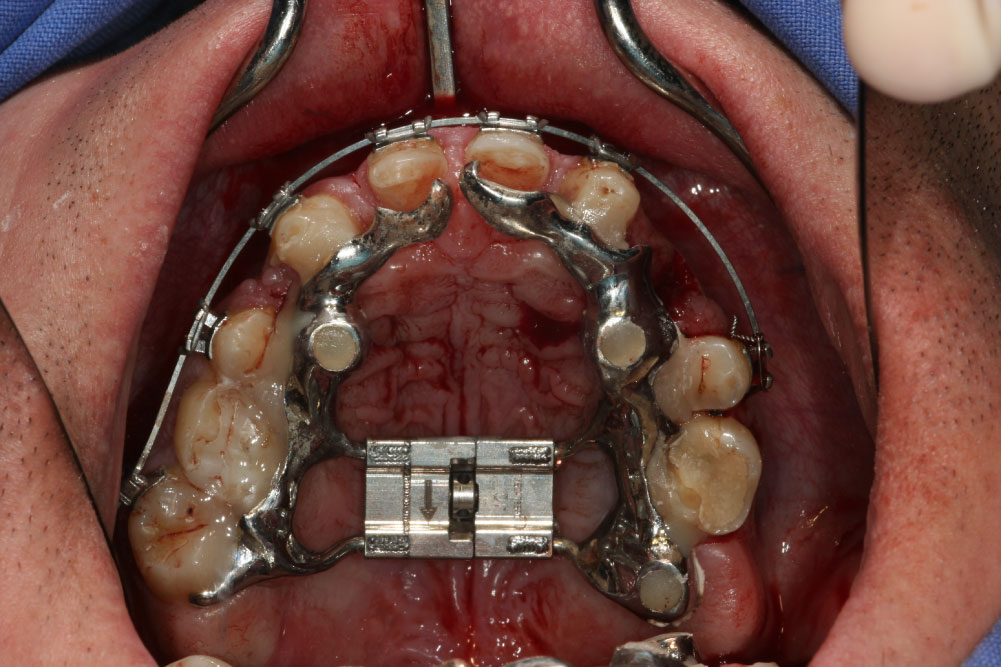

Maxillofacial surgery

After CBCT analysis of the dental and skeletal anomalies and analysis of lateral cephalograms concerning skeletal and soft tissue profile, the patient got presurgical orthodontic treatment. Because of the low dento-alveolar stability, the first surgical intervention concerned the transpalatal distraction. Surgery took place in our clinic for esthetic dental medicine and facial surgery, Dortmund, Germany. After removal of a 1 cm × 0.3 mm piece of gingival transpalatal distraction device was inserted on implants regio palatal 12, 22, 16, 26 (Figure 5 (IGPD)). We used Surgi-Tec TPD All-in-One 2.5 mm, which has been proved to fit well for transverse palatal distraction. Anesthesia was done by Ultracain DS forte. The distractor was fixed with osteosynthesis screws. First activation was performed for 2 mm, second one for 1 mm and the third one for 10 mm. An iliac cortico-spongy chip was prepared and inserted in the palate extension.

Figure 5: Custom made implant guided palatal distractor before activation. View Figure 5